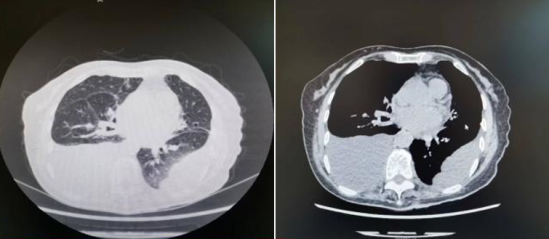

肺部HRCT影像如下:

7月20日胸部+腹盆部增强CT↑

从肺部HRCT可见双侧胸腔积液(左肺部分包裹性积液)伴邻近肺组织膨胀不全,对比2022年7月8日影像学发现:右侧胸腔引流管置入,新增右侧少许气胸,右侧胸腔积液较前减少,左侧胸腔积液较前增多;两肺散在条索影伴渗出较前进展;腹部较前变化不大,盆腔少量积液。2022年7月15日,患者再次行右侧胸腔闭式引流。